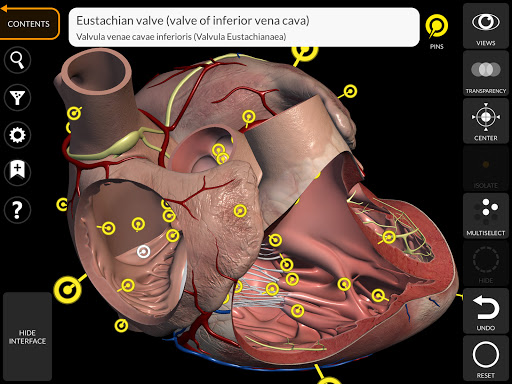

Thông qua giao diện đơn giản và trực quan, bạn có thể quan sát mọi cấu trúc giải phẫu từ mọi góc độ.

Các mô hình giải phẫu 3D đặc biệt chi tiết và có kết cấu lên đến độ phân giải 4k.

• Hệ thống tim mạch

• Xoay và phóng to từng mô hình trong không gian 3D

• Bằng cách chọn một mô hình hoặc một ghim, thuật ngữ giải phẫu liên quan sẽ hiển thị

• Các thuật ngữ giải phẫu và giao diện người dùng có sẵn bằng 11 ngôn ngữ: tiếng Latin, tiếng Anh, tiếng Pháp, tiếng Đức, tiếng Ý, tiếng Bồ Đào Nha, tiếng Thổ Nhĩ Kỳ, tiếng Nga, tiếng Tây Ban Nha, tiếng Trung, tiếng Nhật và tiếng Hàn

• Các thuật ngữ giải phẫu có thể được hiển thị bằng hai ngôn ngữ cùng lúc